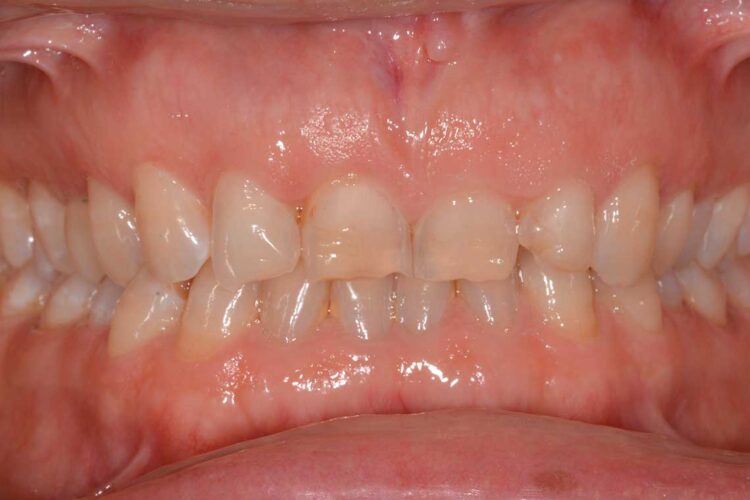

Ortodonzia allineatori – caso clinico 2